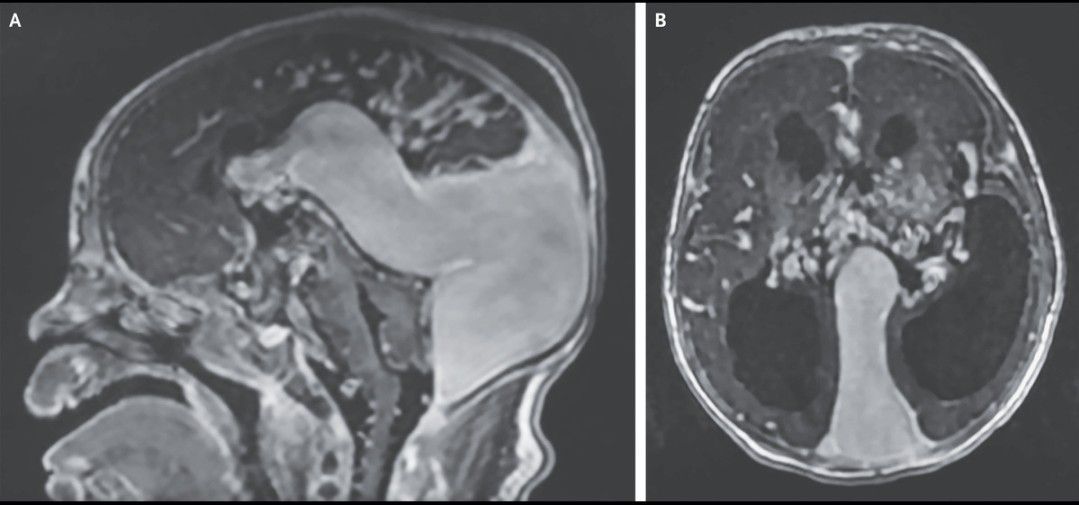

A neonate born at 37 weeks of gestation had respiratory distress 3 hours after birth. A physical examination was notable for subcostal retractions, coarse breath sounds in both lungs, and a systolic murmur. A chest radiograph showed cardiomegaly and bilateral pleural effusions, and an echocardiogram showed a patent foramen ovale, a dilated right atrium, a dilated and hypertrophied right ventricle, tricuspid regurgitation, and right-to-left shunting at the patent ductus arteriosus. Cranial ultrasonography and gadolinium-enhanced T1-weighted magnetic resonance imaging revealed a large choroidal type of vein of Galen malformation, hydrocephalus, and atrophy of the brain stem and cerebellum in the sagittal (Panel A) and axial (Panel B) views. Vein of Galen malformations are rare congenital arteriovenous fistulas in the brain that can result in heart failure and pulmonary hypertension in neonates. Supportive and endovascular treatments have been shown to prolong survival, but the prognosis remains poor with varying neurodevelopmental outcomes. The patient underwent staged endovascular embolization of the malformation. Despite treatment, which also included mechanical ventilation and the use of vasopressors, inhaled nitric oxide, diuretic agents, and prostaglandin E1, the patient had worsening pulmonary edema, liver failure, and renal failure and died 21 days after birth.